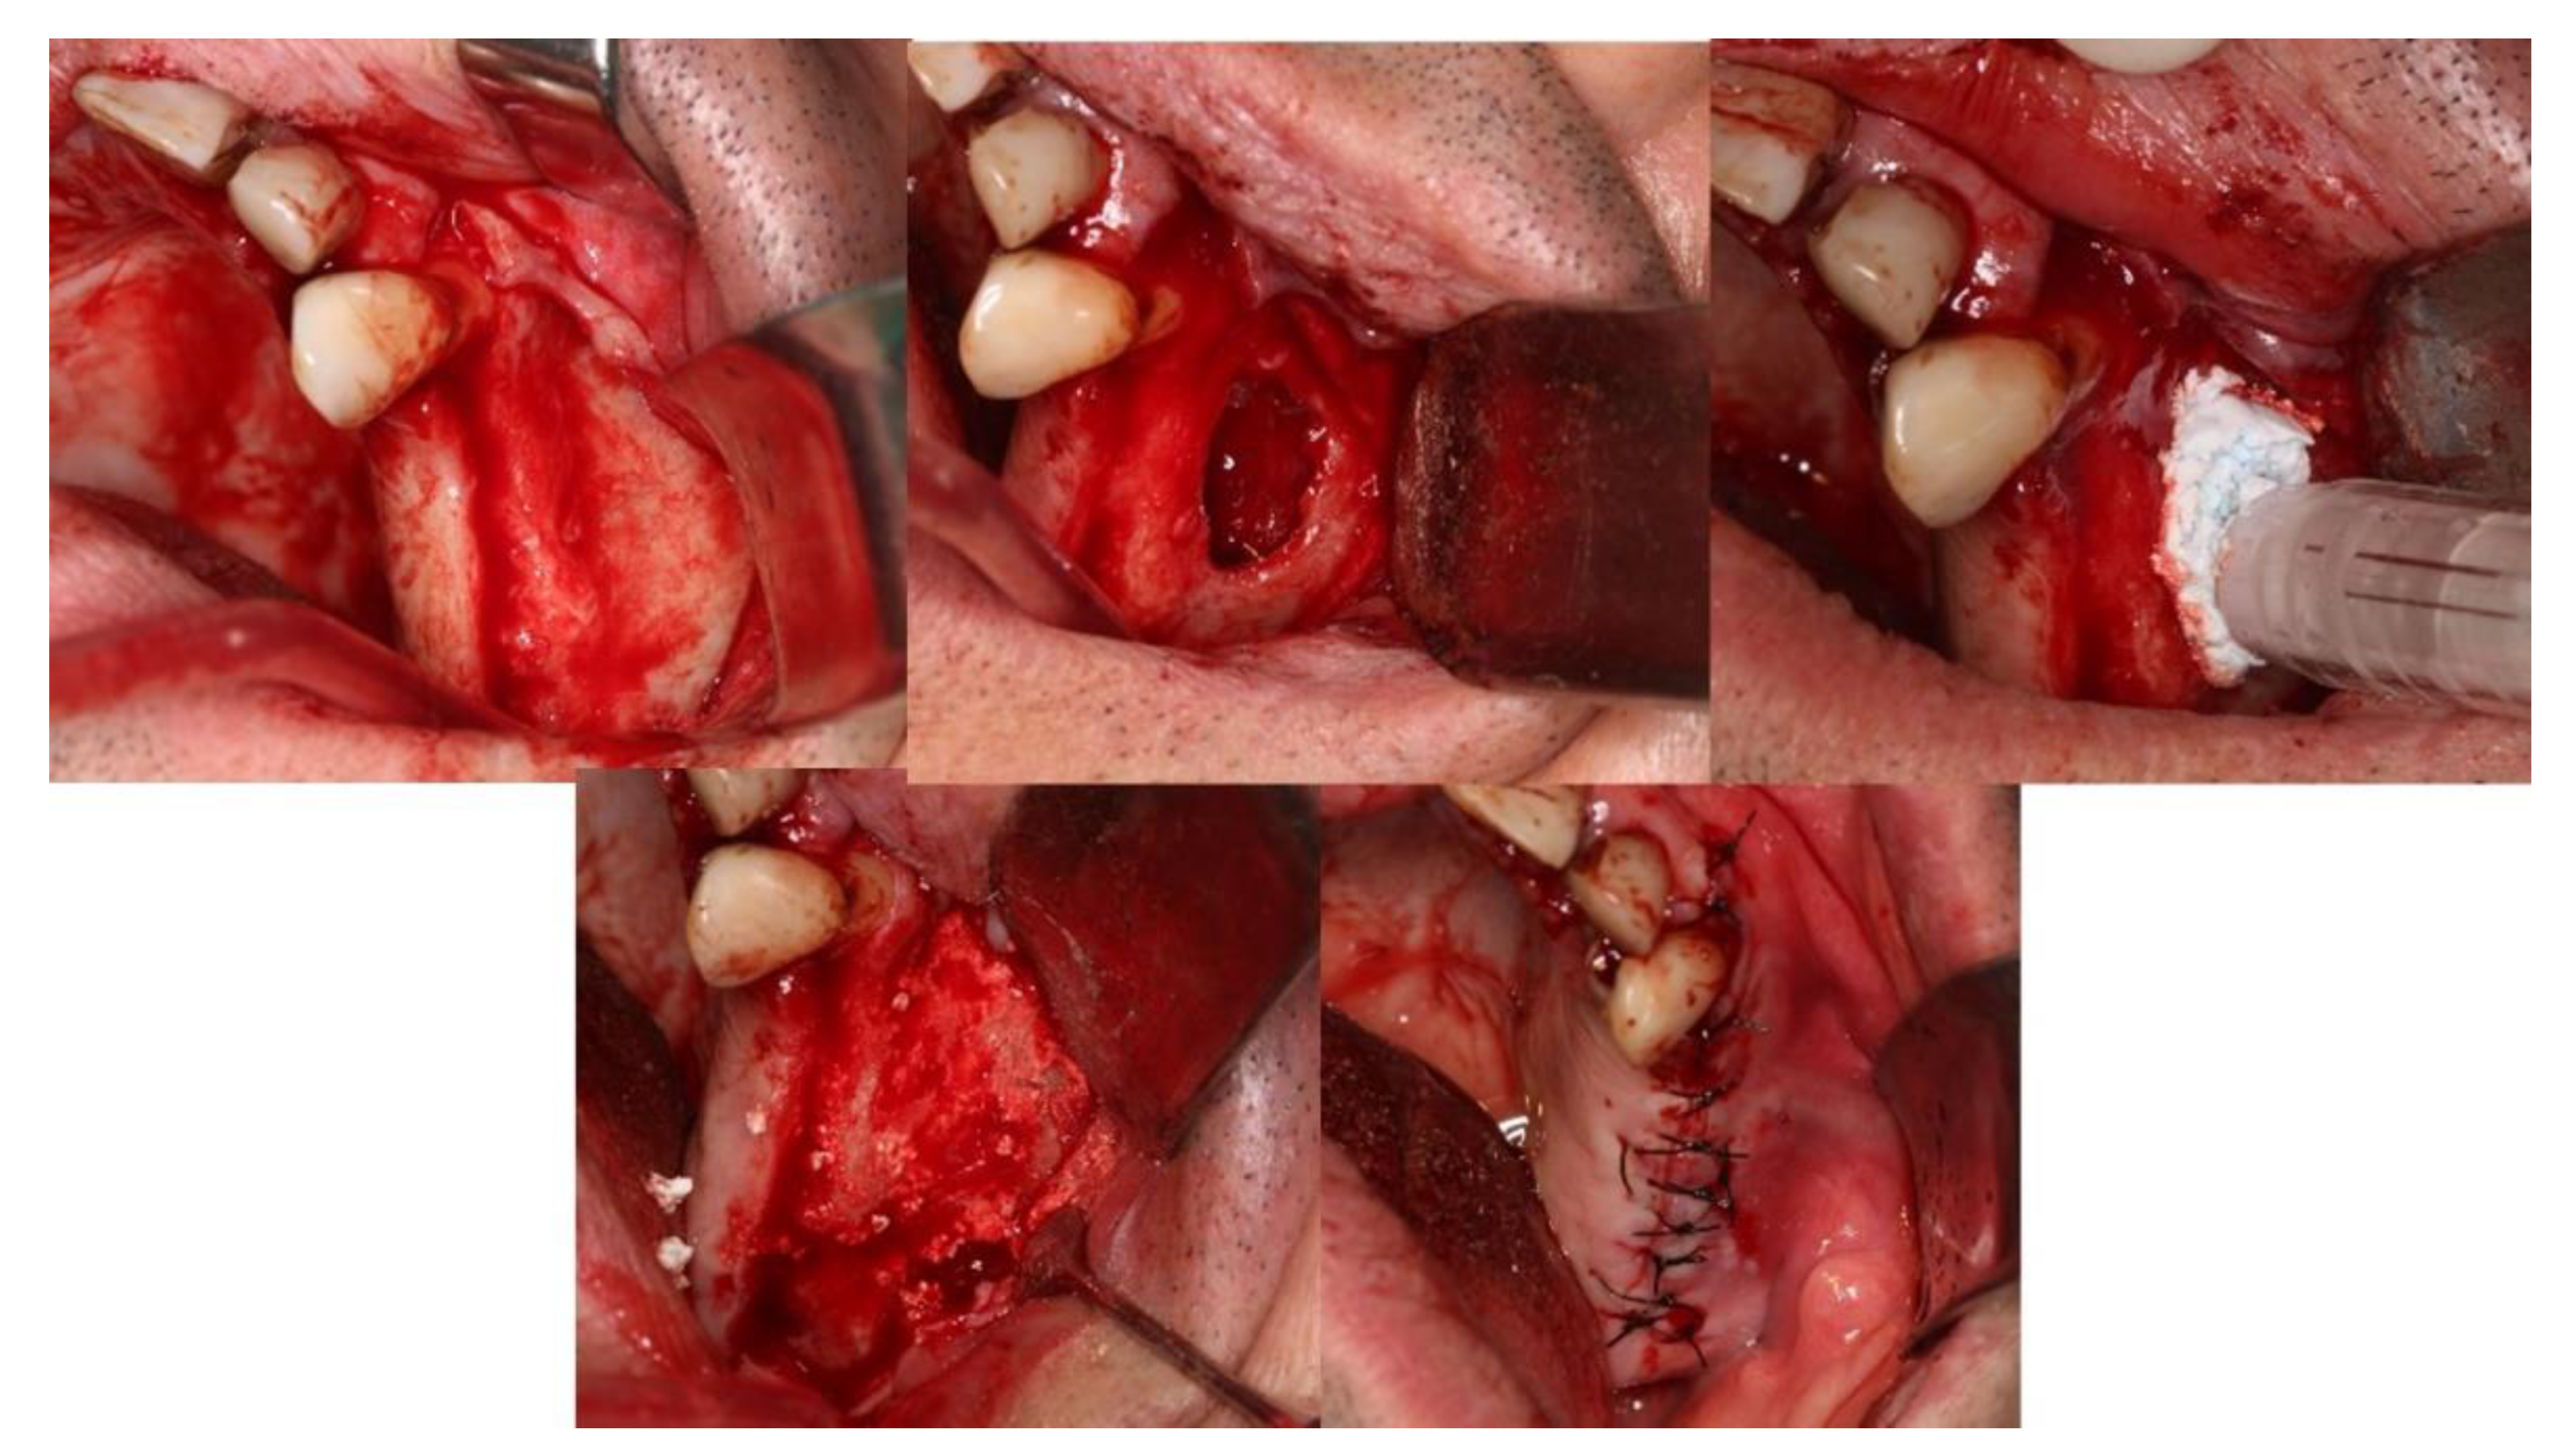

4. Clinical Cases

4.1. Patient No. 1

4.2. Patient No. 2

4.3. Patient No. 3

4.4. Patient No.4

4.5. Patient No.5

4.6. Patient No.6